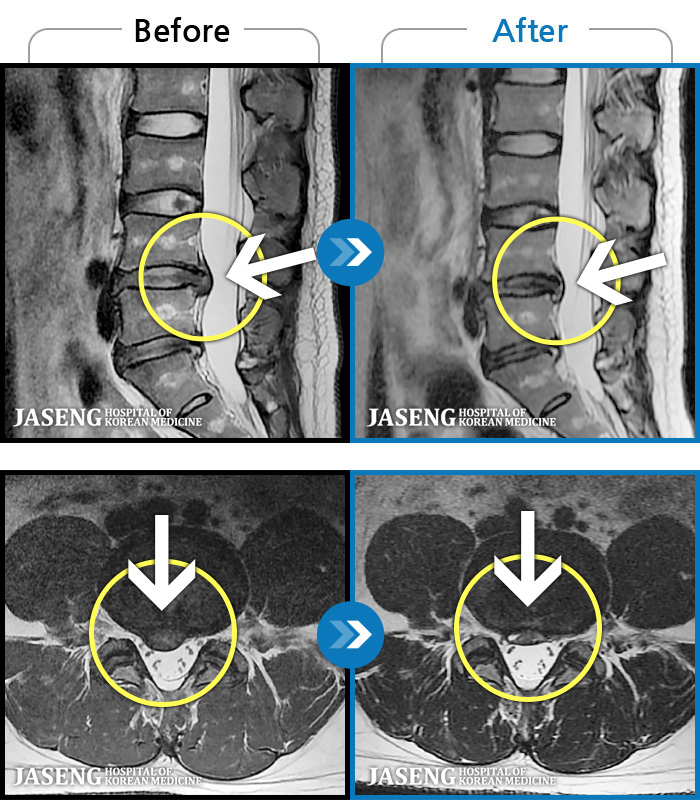

MRI ġ

1,304 MRI ũ ʸ Ȯϼ.